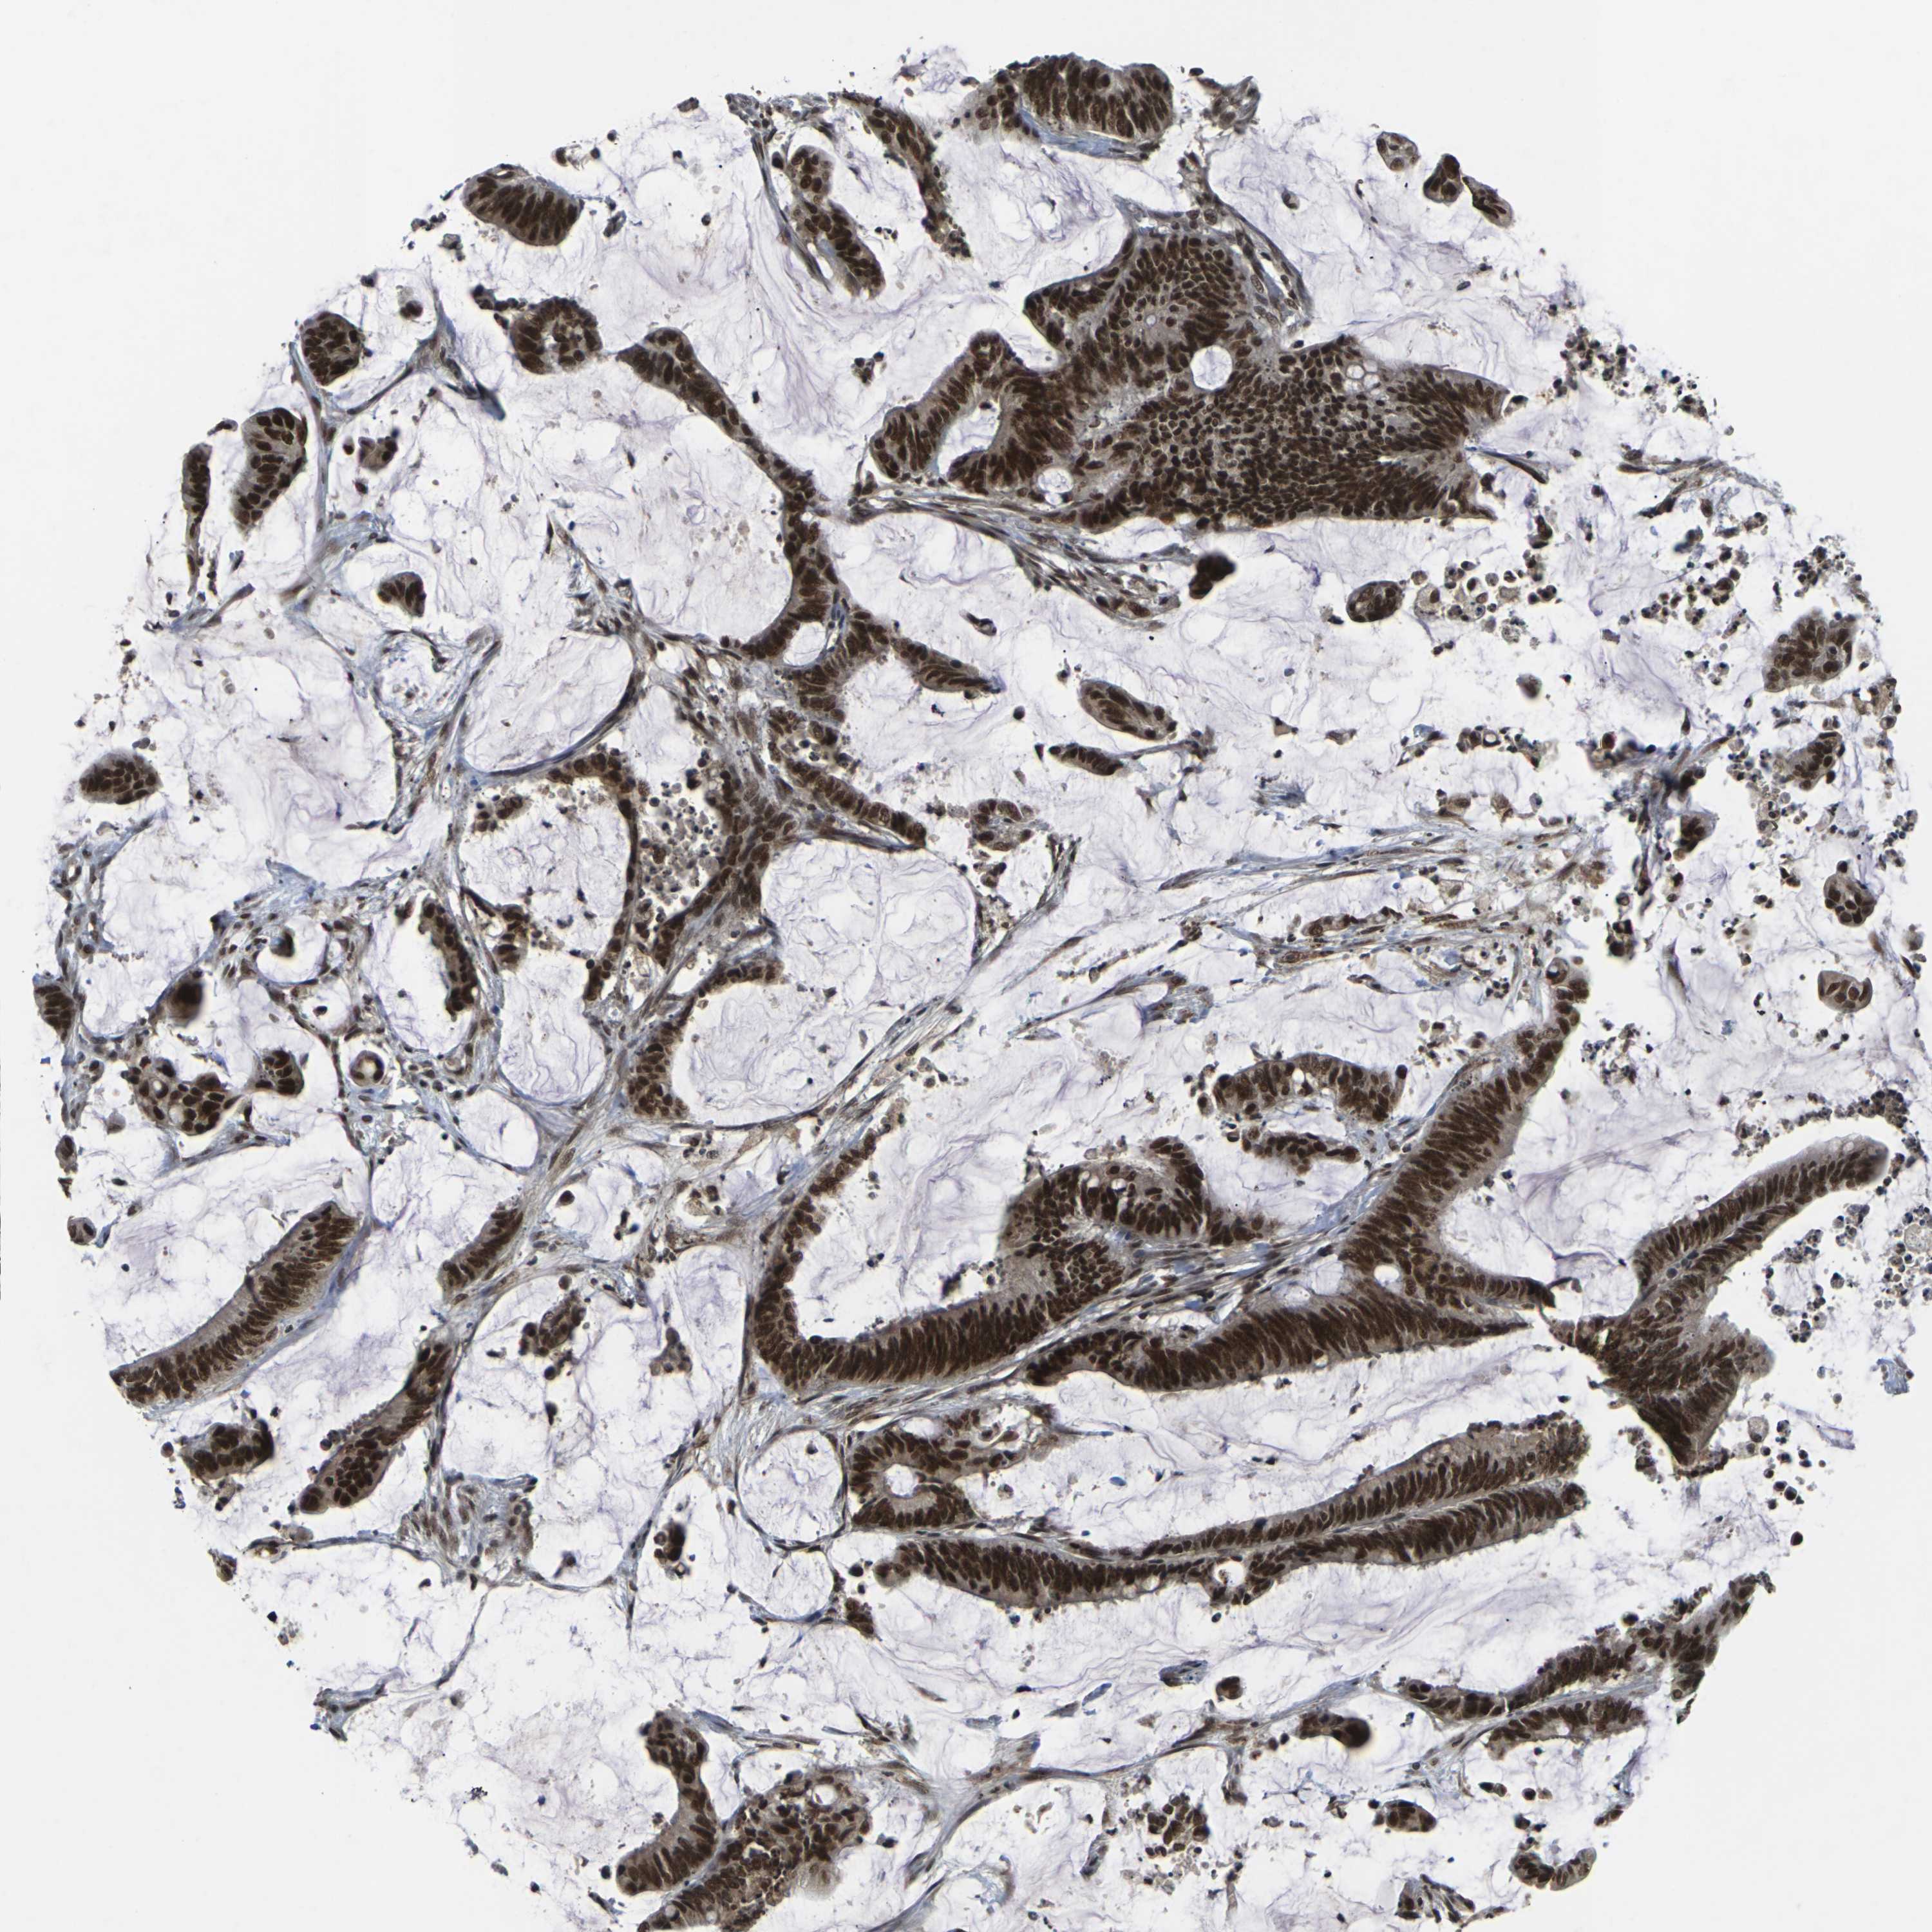

CANCER COLORECTAL CANCER Show tissue menu

Colorectal cancer

Human cancer

Colon adenocarcinoma